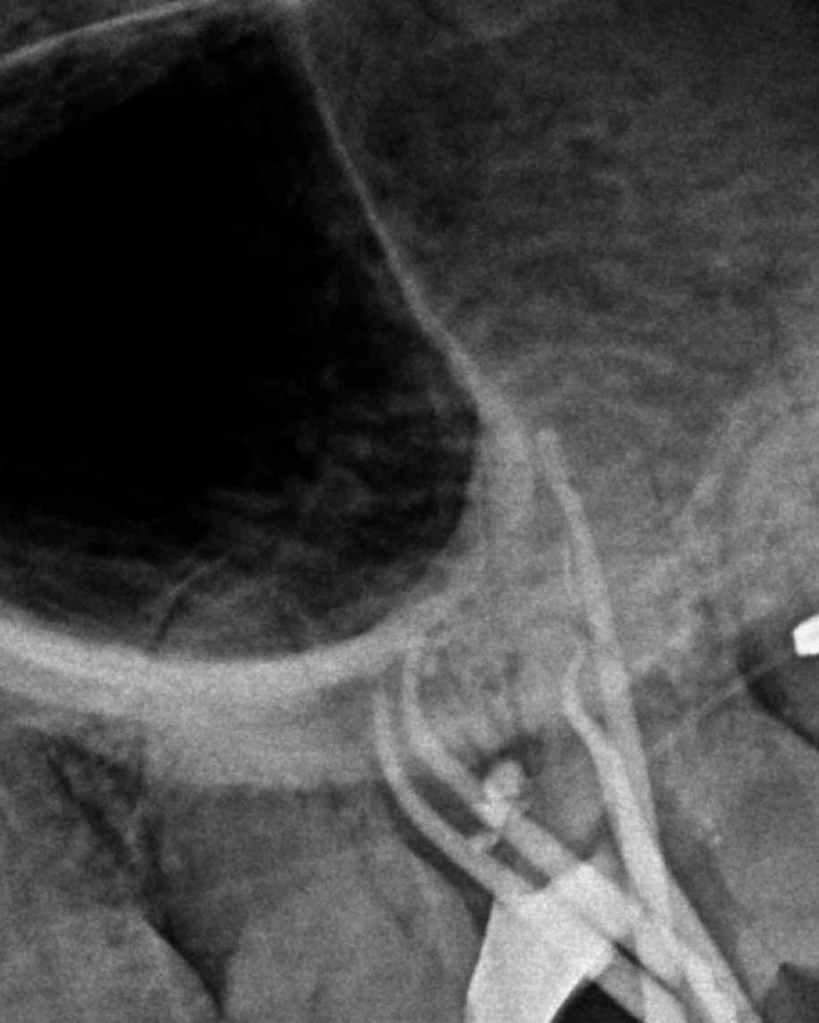

Bifurcación conducto palatino apical